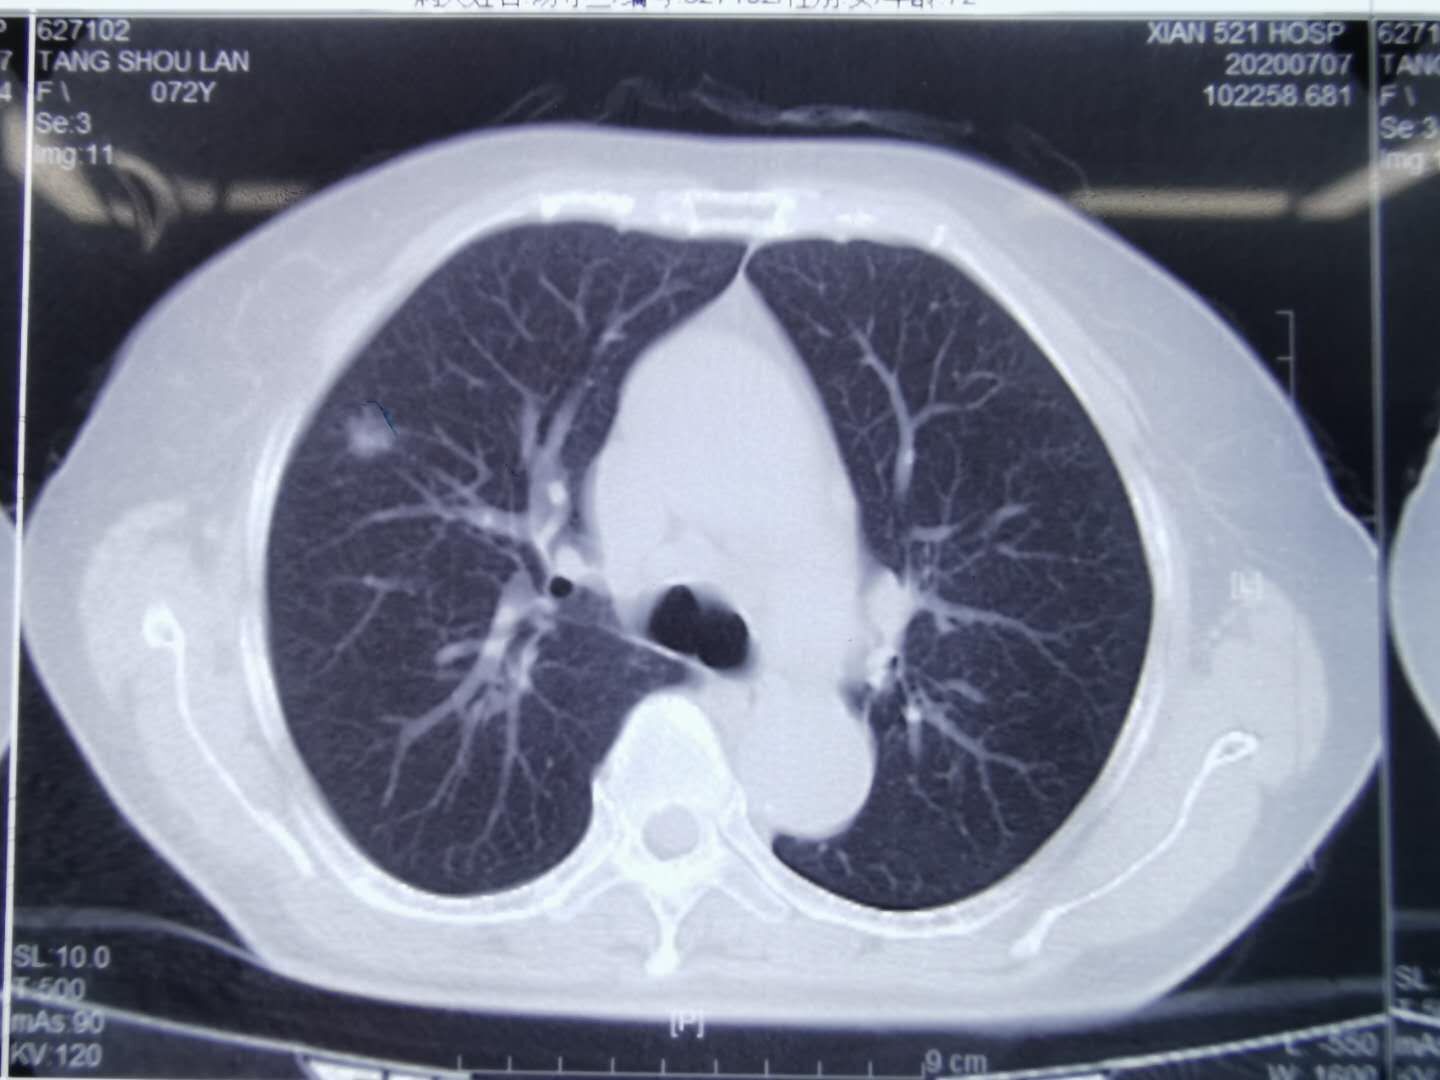

相对显得比较散总体印象:患者两肺多发病灶,其中左上叶以及右侧另处均

图片尺寸932x831